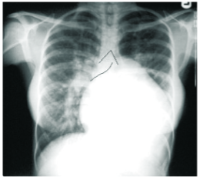

Results: Clinical assessment of the patient showed the following; palpitations, easy fatigability, cough, finger clubbing, orthopnoea, and lately significant precordial hyperactivity and tachypnoea on exertion. The chest x-ray and cardiac ultrasonography showed structural defects consisting of hypoplastic ascending aortic arch, with aortic root overriding inter-ventricular septal defect, right heart chamber enlargement, and congested pulmonary outflow track.

Conclusion: There was hypoplastic ascending aortic trunk (instead of hypoplasia of pulmonary trunk) a slight variation from the components of Tetralogy of Fallot. The probability is that this may have sustained the patient to adult hood. This is a rare occurrence in literature. Limitation of evaluation is also discussed.